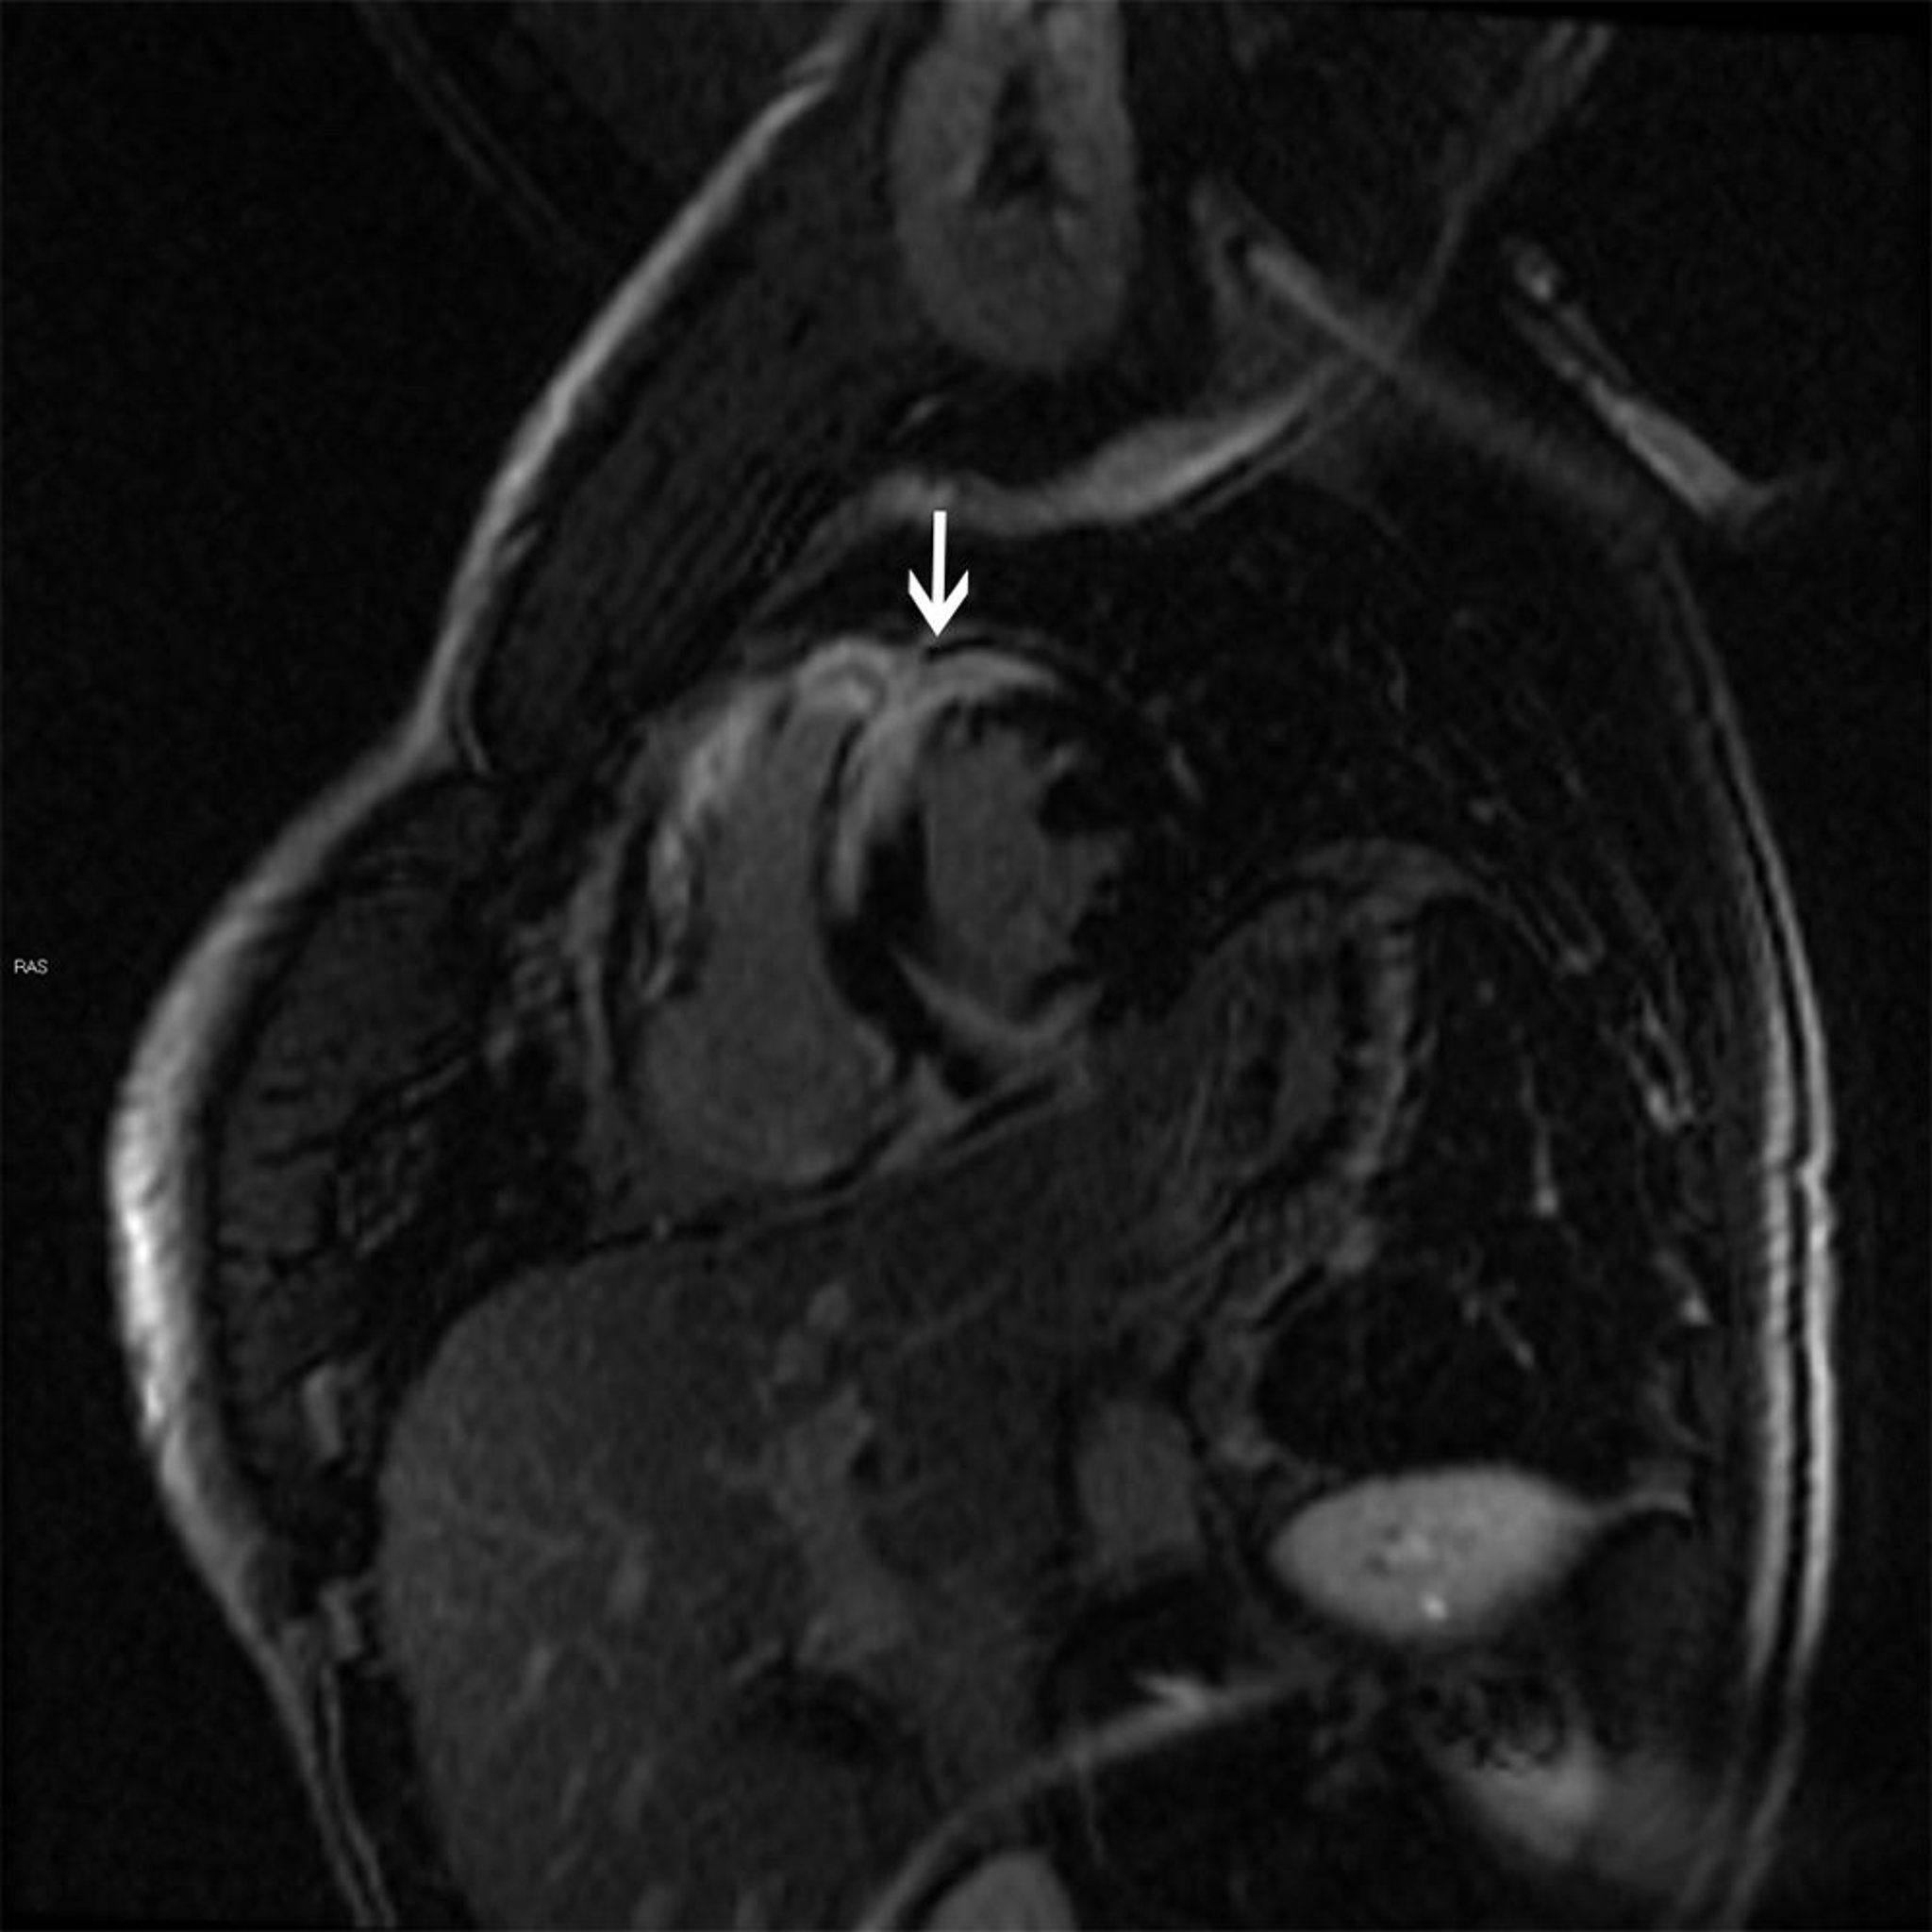

Hallazgos en la resonancia magnética de la sarcoidosis cardíaca

Esta resonancia magnética cardíaca muestra un patrón de realce transmural tardío con gadolinio en parches (flecha) característico de la sarcoidosis, que puede causar una miocardiopatía dilatada o hipertrófica.